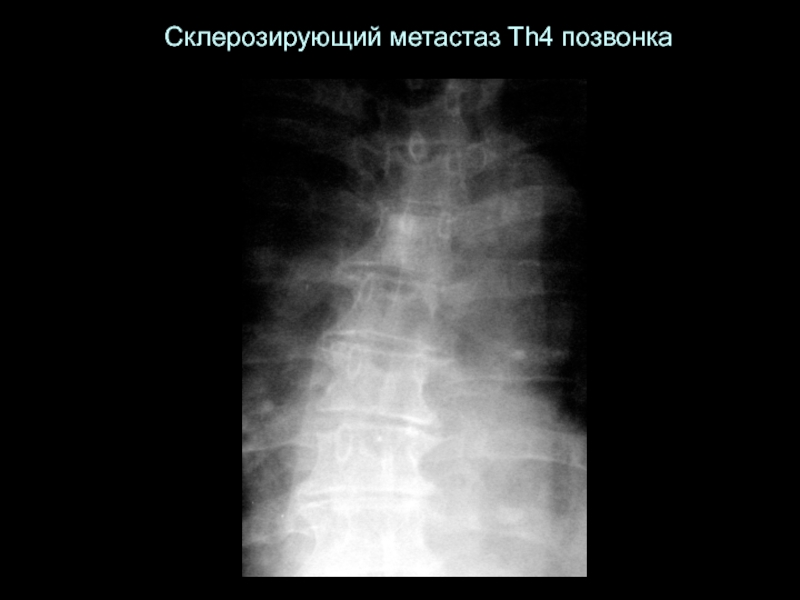

Слайд 44Склерозирующий метастаз Th4 позвонка

Склерозирующий метастаз Th4 позвонка